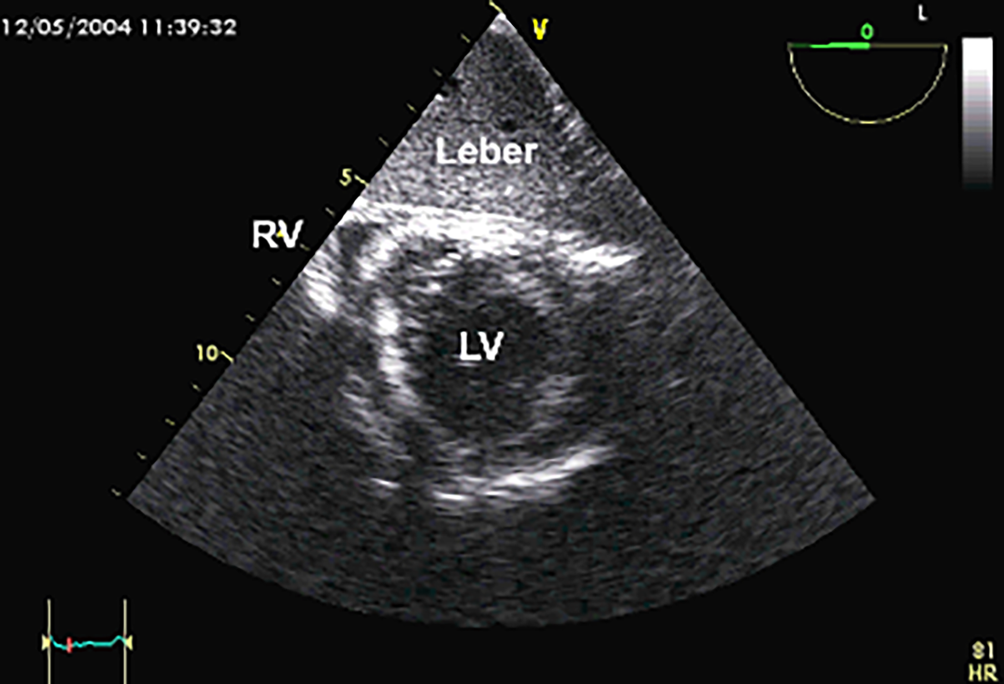

Anlotebene: kurze Achse

Sondenposition: transgastrisch

Rotationswinkel: 0°